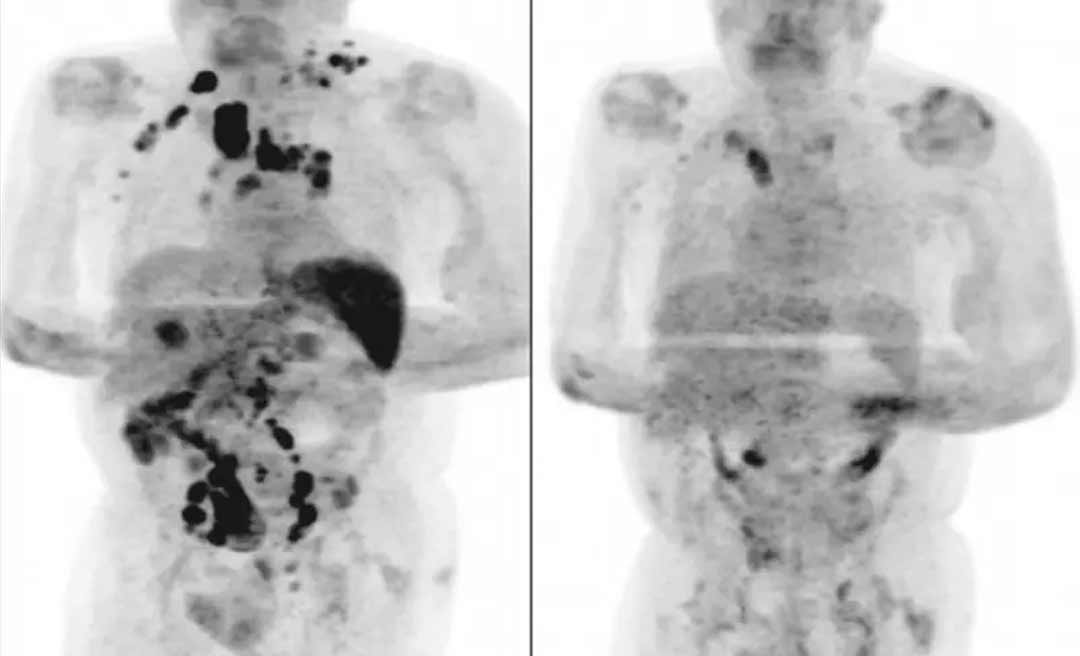

Quatro meses depois, os médicos afirmaram que o inchaço dos nódulos havia diminuído. Um exame de tomografia revelou a remissão generalizada do linfoma.

A hipótese levantada pelos autores do artigo é de que a infecção pelo novo coronavírus desencadeou uma resposta imune contra o tumor. As citocinas inflamatórias produzidas em resposta à infecção poderiam ter ativado células T específicas com antígenos tumorais e células que naturalmente agem contra o tumor.